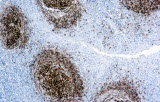

- Pannelli orientati alle entità per neoplasie linfoidi:

- Linfoma follicolare: tipici pattern di co-espressione (es. CD10 con BCL2 aberrante).

- Linfoma a cellule mantellari: ciclina D1 e SOX11 come marcatori chiave, incluso supporto per i casi ciclina D1 negativi.